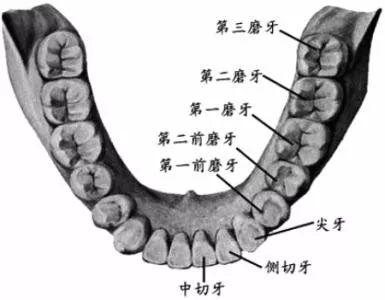

智齒,學(xué)名三大臼(jiù)齒,又叫做第三磨牙。

雖然叫做智齒,但其實(shí)和智商毫無(wú)關(guān)系...只是一般在 18 歲后長(zhǎng)出來(lái),正處于人類智力發(fā)育的鼎盛期而得名(小時(shí)候看鄭淵潔的《智齒》,一直對(duì)自己沒有長(zhǎng)智齒而耿耿于懷,現(xiàn)在,悔之晚矣...)。

人類在進(jìn)化過(guò)程中,進(jìn)食的食物是越來(lái)越精細(xì),頜骨(就是你的下巴)越來(lái)越短,但牙齒不會(huì)減少,有的牙齒就沒有空間長(zhǎng)出來(lái)。嚴(yán)肅的推斷出「智齒長(zhǎng)不好,說(shuō)明你臉小」(強(qiáng)行安慰一波長(zhǎng)阻生智齒的人)...